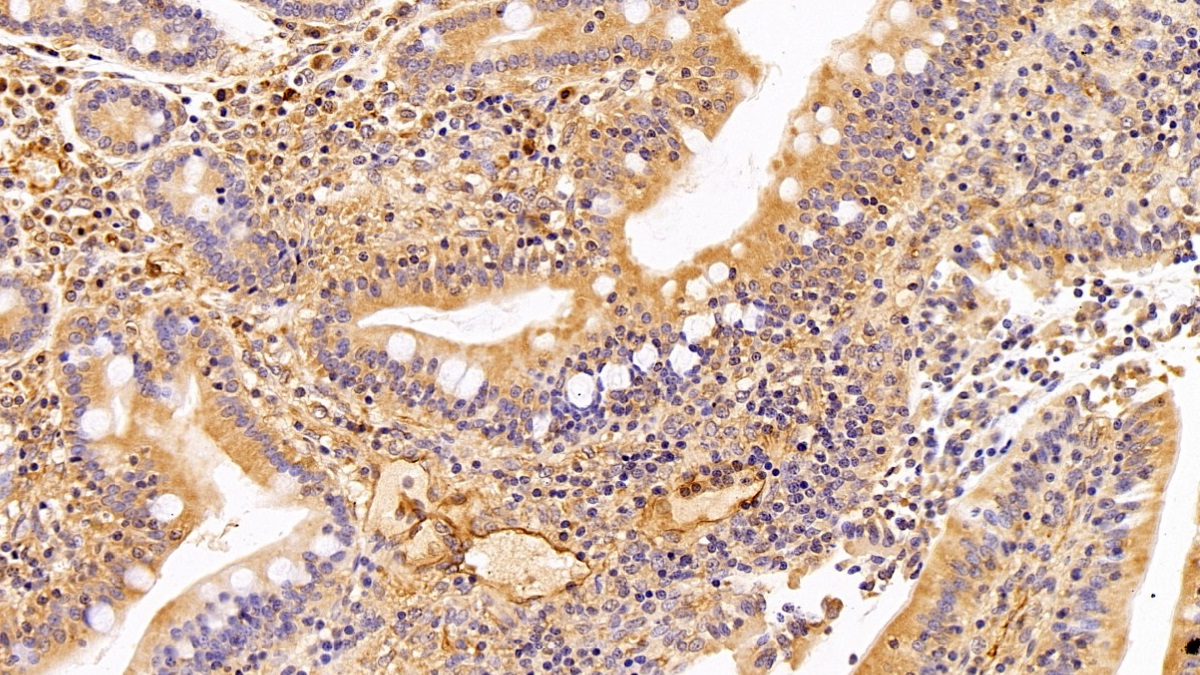

Использование высококачественных первичных антител является неотъемлемым условием получения точных и воспроизводимых результатов в современных научных исследованиях. Например, в рамках онкологического исследования удалось достоверно идентифицировать экспрессию белка PD-L1, что сыграло ключевую роль в оценке потенциальной эффективности иммунотерапии. Применение надежных антител обеспечило стабильность сигнала и высокую специфичность детекции, что позволило получить данные, пригодные для публикации в рецензируемых научных изданиях.